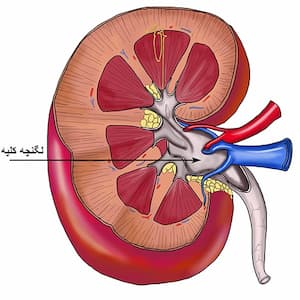

سنگ لگنچه کلیه چیست و چرا درمان آن اهمیت دارد؟

لگنچه کلیه (Renal Pelvis) در واقع بخش مرکزی و قیف مانند کلیه است که ادرار در آن جمع شده و سپس به سمت لوله های حالب هدایت می شود. تشکیل سنگ لگنچه کلیه می تواند باعث انسداد مسیر ادرار و بروز دردهای شدید کلیوی شود. علائم سنگ لگنچه کلیه معمولاً شامل درد مبهم یا شدید در پهلو، تهوع و گاهی مشاهده خون در ادرار است.

سنگ لگنچه کلیه به رسوبات سختی گفته می شود که در بخش مرکزی کلیه (لگنچه) تشکیل شده و مانع از جریان طبیعی ادرار می شود.